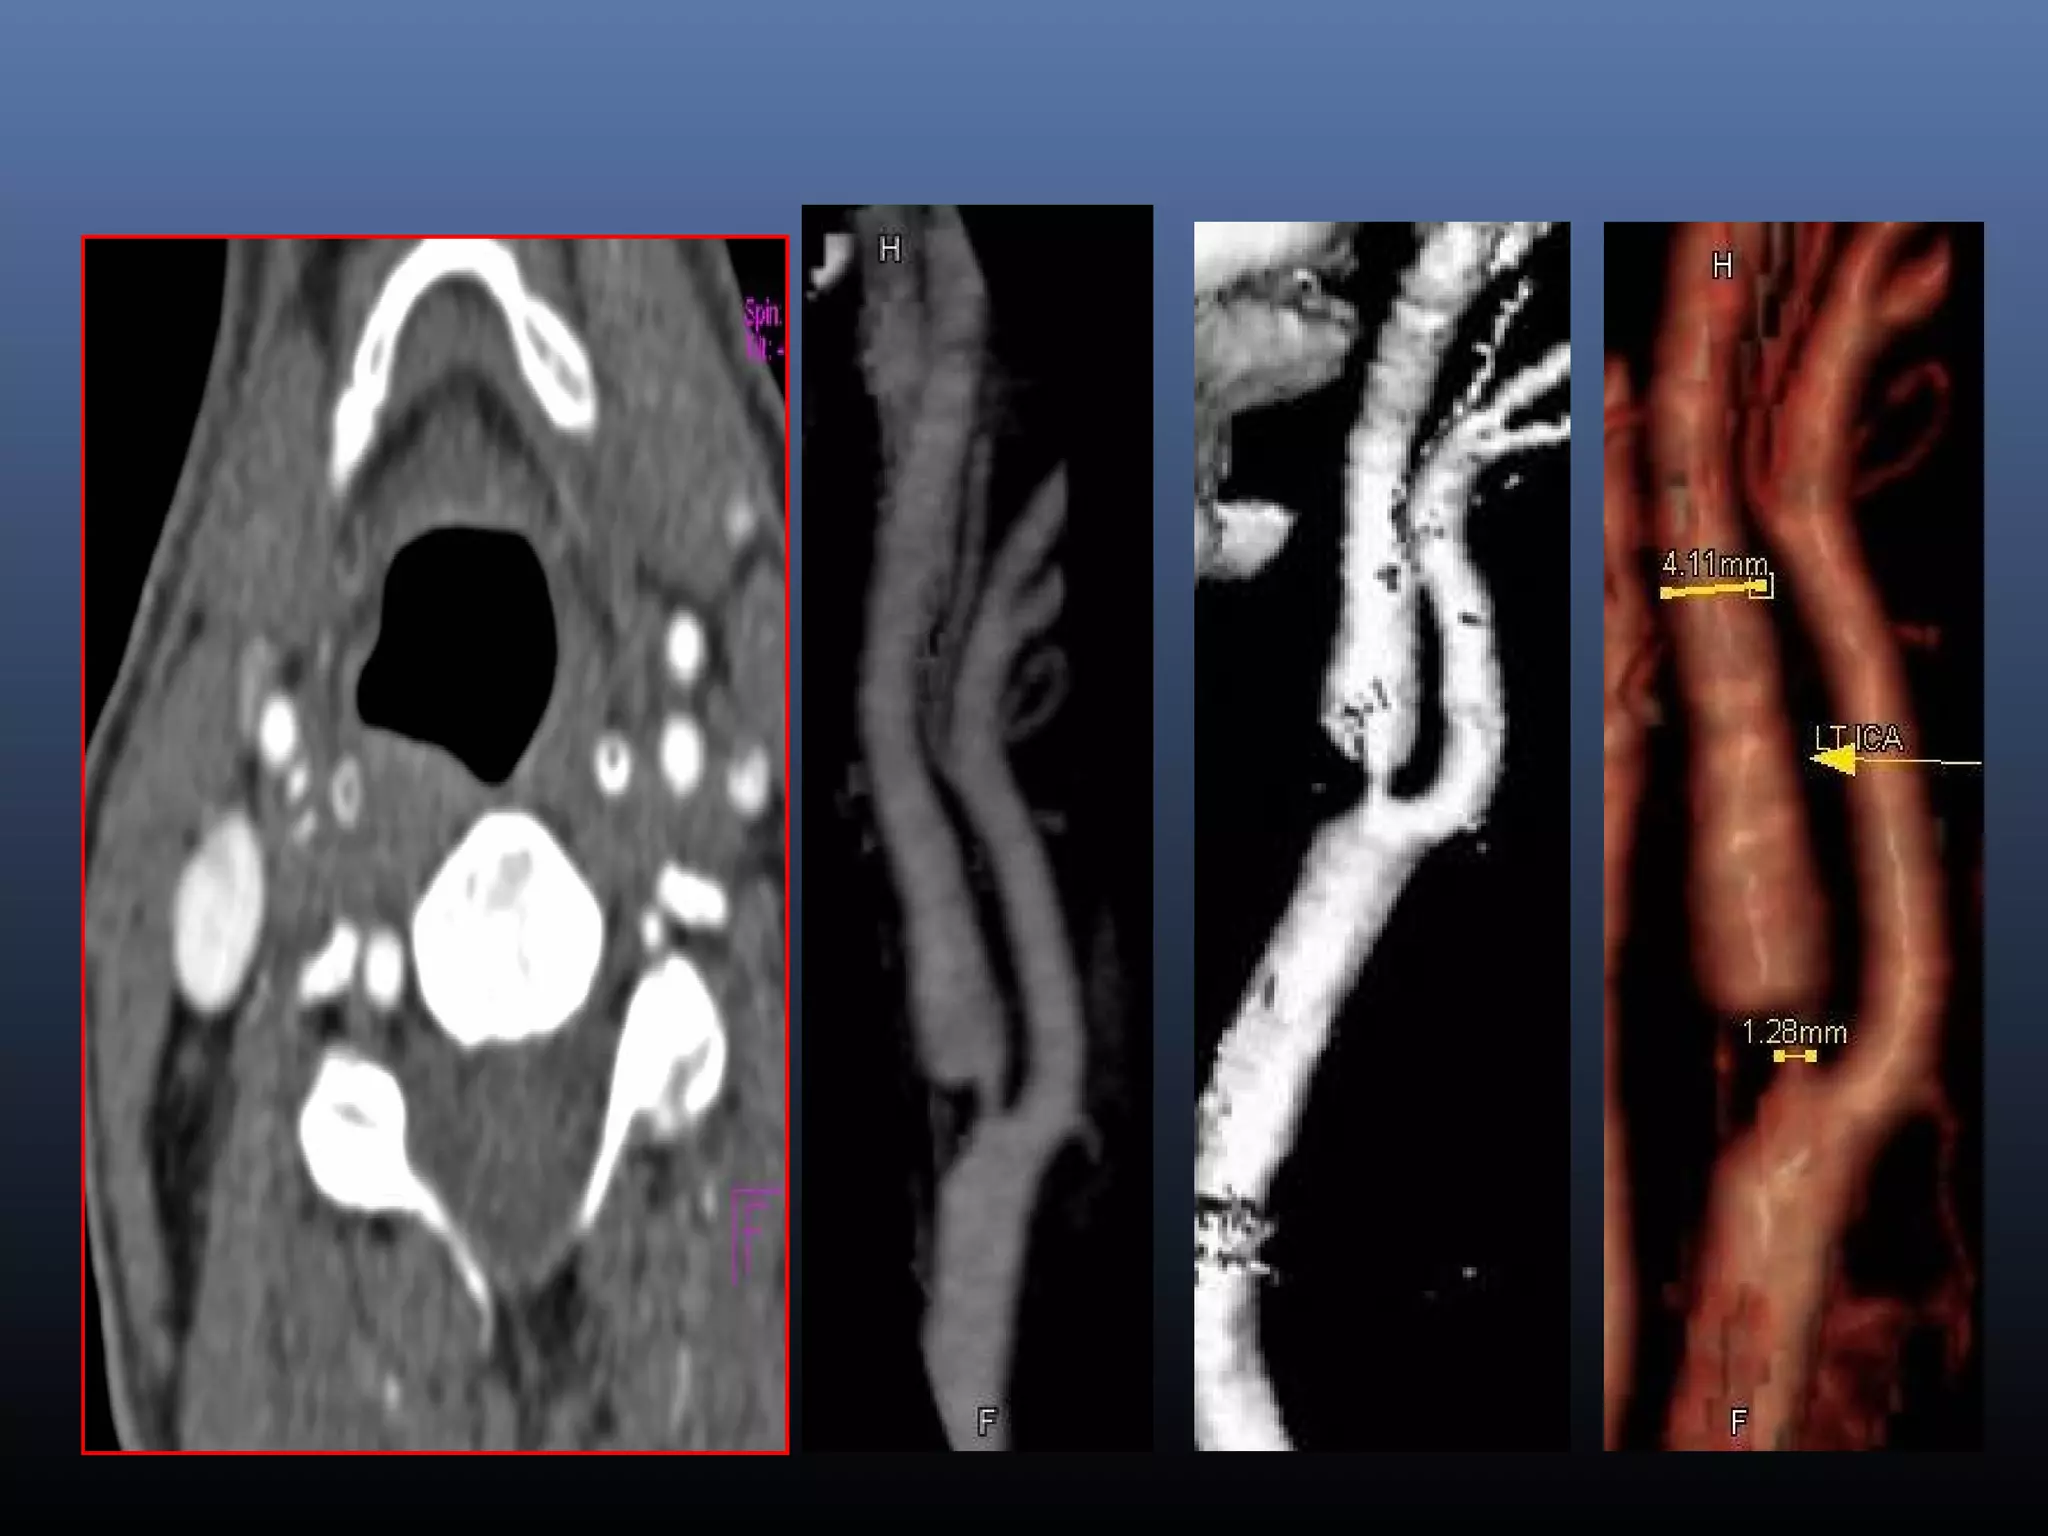

CAROTID DISSECTION

• 118.

Dissection  Imaging techniqueof choice  MRA -2D TOF ,DSA- Gradual irregular tapering,stenosis, Distal emboli, psedoaneurysms Non contrast fat supressed T1 sequence at base of skull and neck- crescentic hyperintensity in vessel mura

• 119.

• 120.

• 121.